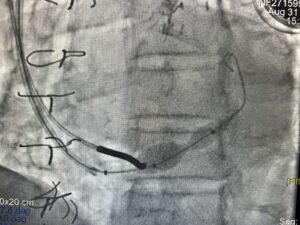

Zabieg wykonywany jest z nakłucia żyły szyjnej i polega na kontrolowanym zwężeniu zatoki wieńcowej przy użyciu rozprężalnego na balonie stentu o kształcie klepsydry. Wskutek zabiegu dochodzi do stopniowego zwężenia pola przepływu przez zatokę wieńcową z redystrybucją przepływu krwi z obszarów o lepszym do obszarów o gorszym ukrwieniu mięśnia sercowego.